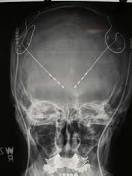

Ohio State study offers hope for brain-injury victims Mysiw, who has been working with traumatic brain injury patients for years, selected four patients for the study. Two often behaved inappropriately and ...